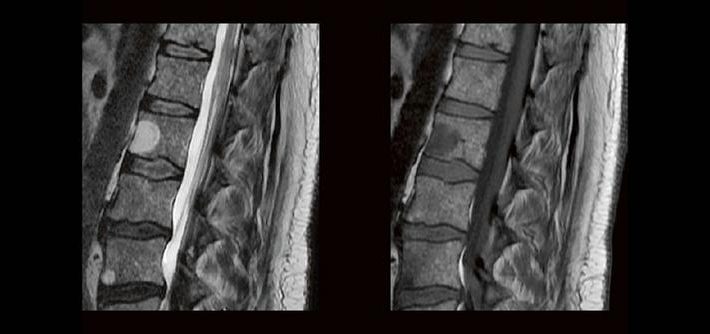

Blickdiagnosen im MRT für MTR (Webinar | Online)

Dorina Petersen In der täglichen Routine hat man wenig Zeit, sich lange mit den Bildern zu beschäftigen, die man anfertigt. Dennoch soll man auf bestimmte Erkrankungen richtig reagieren und die Protokolle anpassen. MTR´s sind keine Ärzte, dennoch gibt es ein Krankheiten, die eindeutige Bildmerkmale zeigen. In diesem Webinar werden eine Reihe solche Erkrankungen gezeigt. Woran […]